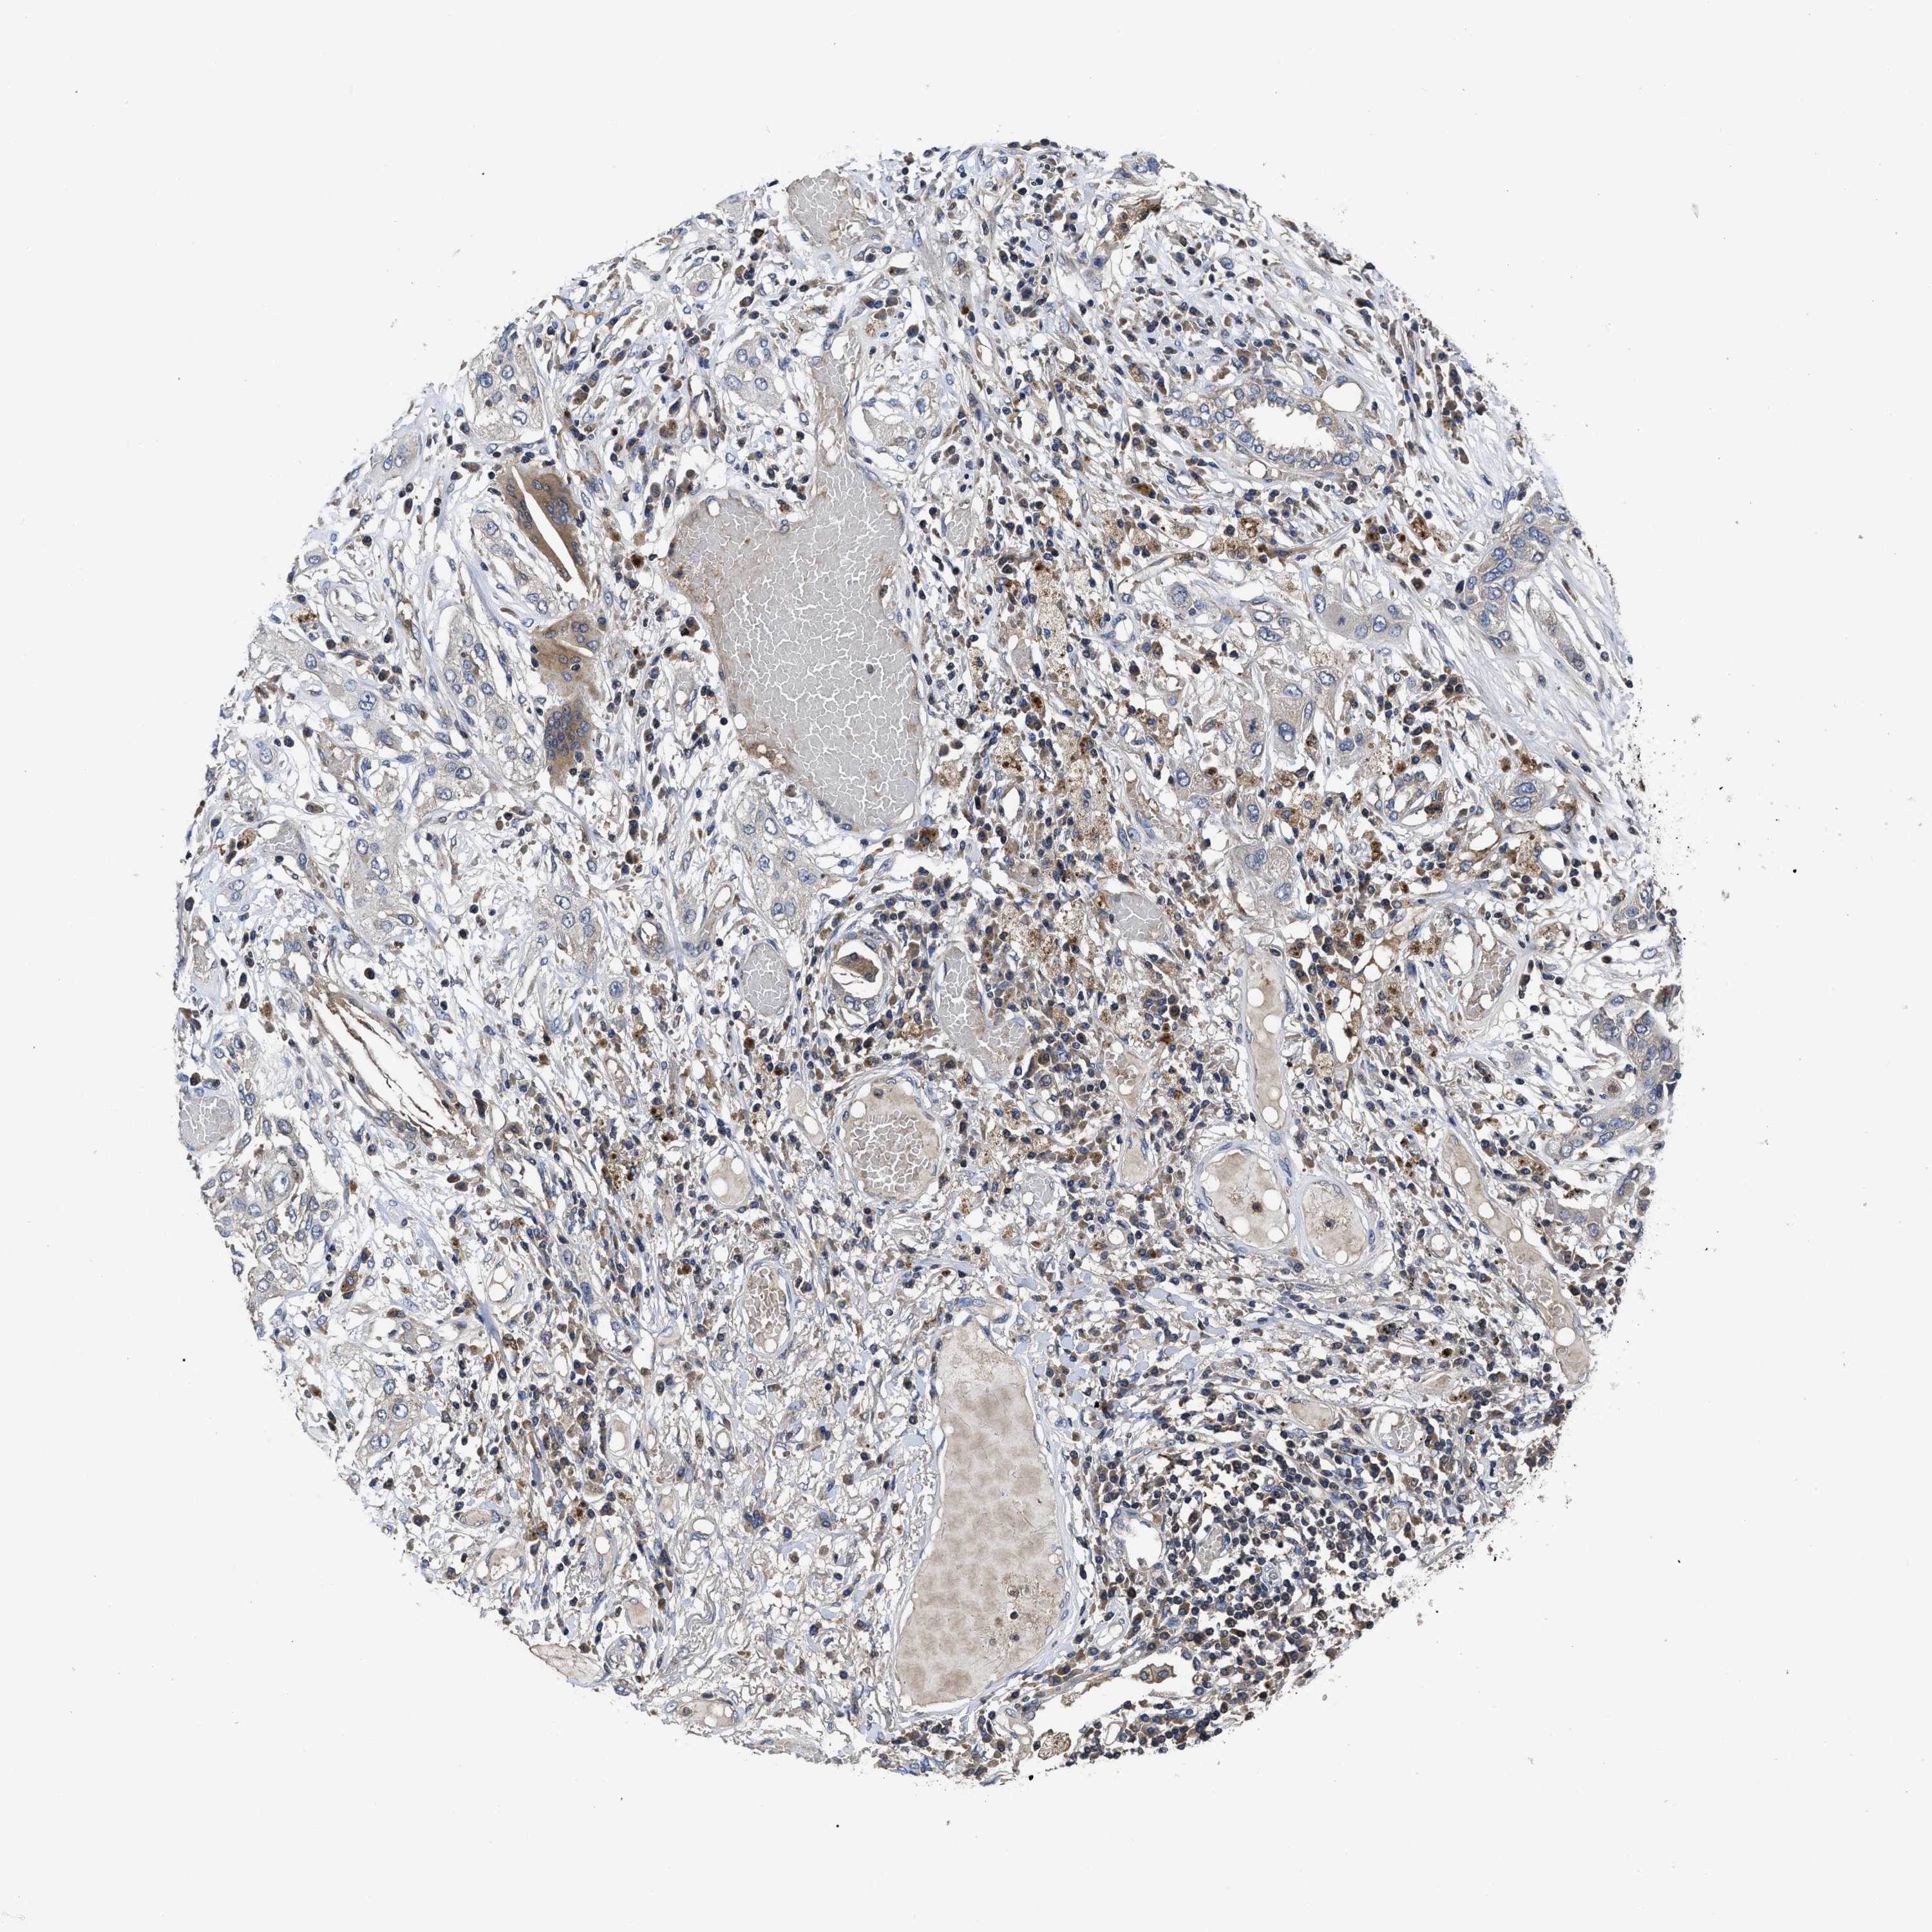

LUNG ADENOCARCINOMA (TCGA) - Interactive survival scatter ploti

The Survival Scatter plot shows the clinical status (i.e. dead or alive) for all individuals in the patient cohort, based on the same data that underlies the corresponding Kaplan-Meier plots. Patients that are alive at last time for follow-up are shown in blue and patients who have died during the study are shown in red.

The x-axis shows the expression levels (FPKM) of the investigated gene in the tumor tissue at the time of diagnosis. The y-axis shows the follow-up time after diagnosis (years). Both axes are complimented with kernel density curves demonstrating the data density over the axes. The top density plot shows the expression levels (FPKM) distribution among dead (red) and alive patients (blue). The right density plot shows the data density of the survived years of dead patients with high and low expression levels respectively, stratified using the cutoff indicated by the vertical dashed line through the Survival Scatter plot. This cutoff is automatically defined based on the FPKM cutoff that minimizes the p-score. The cutoff can be changed by dragging the vertical line or by entering a cutoff value in the square labeled "Current cut-off".

Under the Survival Scatter plot the p-score landscape (black curve; left axis) is shown together with dead median separation (red curve; right axis). Dead median separation is the difference in median mRNA expression between patients who have died with high and low expression, respectively. It is calculated as follows: median FPKM expression of dead patients with high expression - median FPKM expression of dead patients with low expression. This is intended to aid the user in visually exploring custom cutoffs and the associated p-scores and dead median separation.

Individual patient data is displayed and can be filtered by clicking on one or more of the category buttons on the top of the page. Categories describing expression level and patient information include: high, low, alive, dead, female, male and tumor stages. The scale of the x-axis can be toggled between linear and log-scale by clicking on the "x log" button. Mouse-over function shows TCGA ID, patient information and mRNA expression (FPKM) for each patient.

& Survival analysisi

Kaplan-Meier plots summarize results from analysis of correlation between mRNA expression level and patient survival. Patients were divided based on level of expression into one of the two groups "low" (under cut off) or "high" (over cut off). X-axis shows time for survival (years) and y-axis shows the probability of survival, where 1.0 corresponds to 100 percent.

YBEY is not prognostic in Lung Adenocarcinoma (TCGA)

: 17.99

Average pTPM 19.5

Number of samples 497